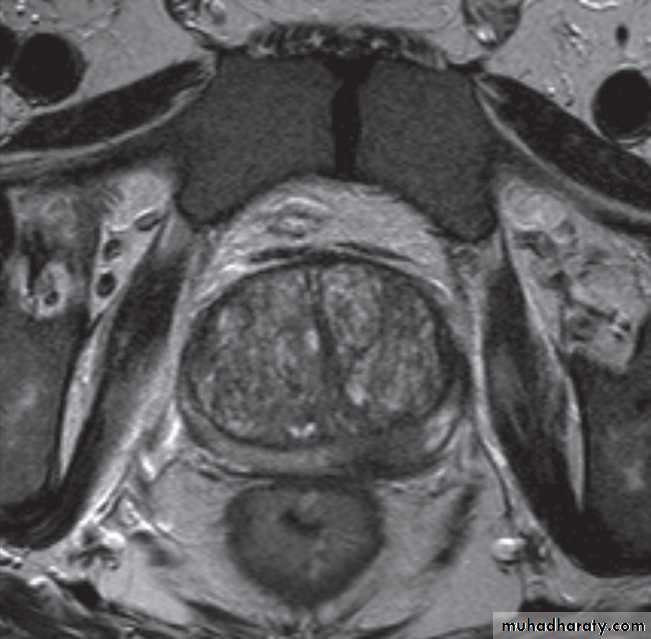

Magnetic resonance imaging is best imaging modality for staging , used to assess early stage prostate cancer in patients being considered for radical surgery or radiotherapy. Tumour in the peripheral zone is seen as a relatively low signal mass within the normal high signal of the peripheral zone on T2-weighted images.

MRI is used to demonstrate extracapsular tumour spread, to show invasion of the seminal vesicles, and to demonstrate possible lymph

node metastases .